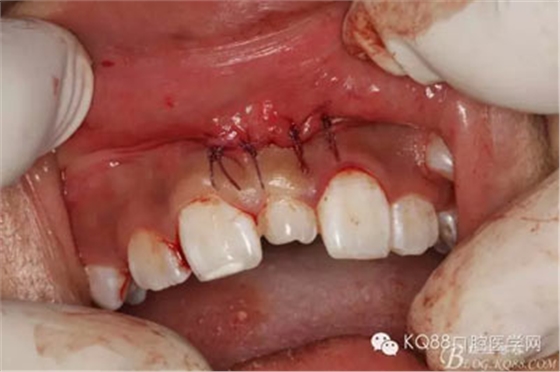

圖17.縫合四針,患者鼻腔正常,無(wú)出血。切口小,手術(shù)簡(jiǎn)單明了,創(chuàng)傷小。

圖18.然后拔除萌出的多生牙,這樣做,可以防止先拔萌出多生牙導(dǎo)致出血多,影像拔埋伏多生牙的手術(shù)視野